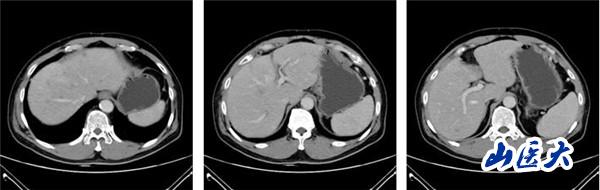

(2022-01-08基線肝臟CT靜脈期)

(2022-08-26復查肝臟CT靜脈期)

該患者在團隊成員仔細閱片、認真討論下,因患者為PD-L1 CPS高表達人群,TMB-H基因狀態。盡管目前國內外胰腺癌診療指南并沒有對該類型患者指明個體化治療策略,但通過查閱近年來已經報道的小樣本臨床研究以及個案報道資料,最終為患者制定了免疫聯合化療治療策略:PD-1單抗+AG治療6周期后,PD-1單抗+卡培他濱維持治療。2022年8月26日,患者再次完善胸腹部CT評價療效后,達到了大PR(部分緩解)的效果。多達20余處肝轉移病灶幾乎消失不見,患者可以正常工作生活。